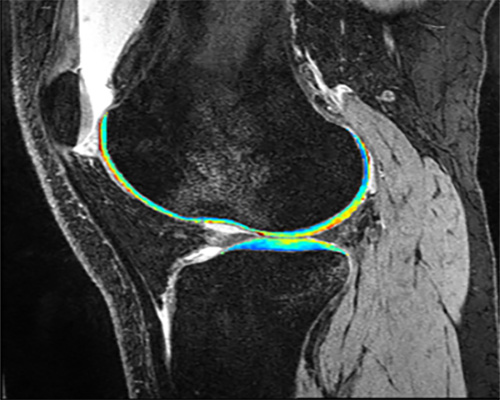

“Multi-Vendor Multi-Site Novel Accelerated MRI Relaxometry”

Li, Xiaojuan

NIH (NIAMS)   —   R01AR077452

"Multi-Vendor Multi-Site Novel Accelerated MRI Relaxometry"

NIH (NIAMS)   —   R01AR075422

"Imaging post-traumatic osteoarthritis 10-years after ACL reconstruction: a multicenter cohort study with quantitative MRI"